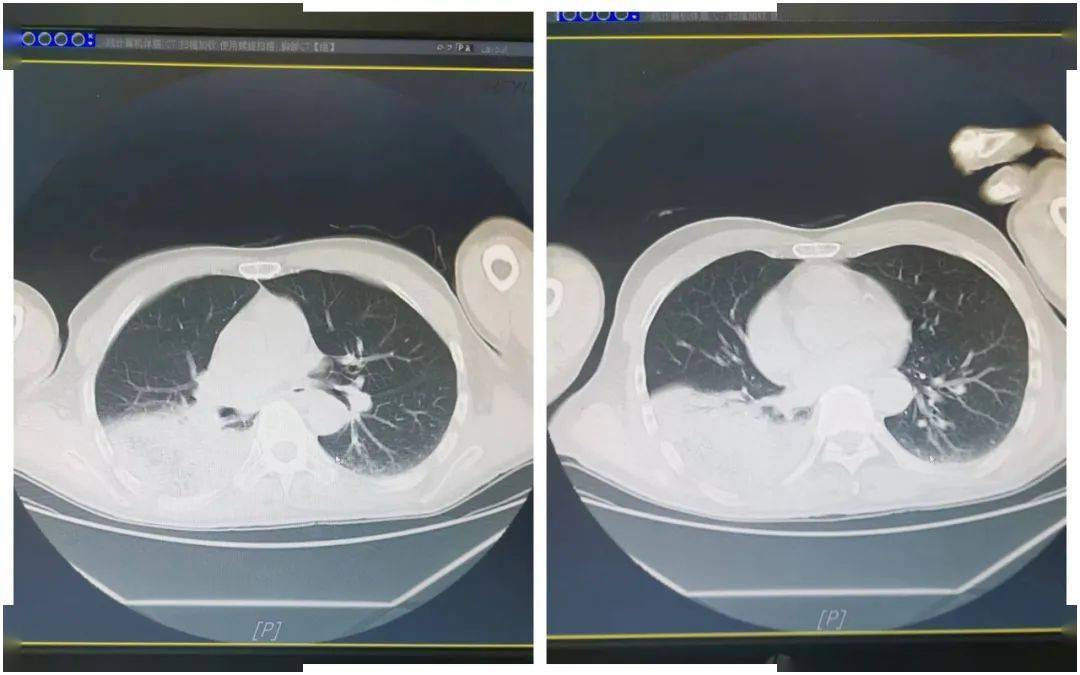

"鹦鹉热"也会热成大白肺?

图片尺寸999x698